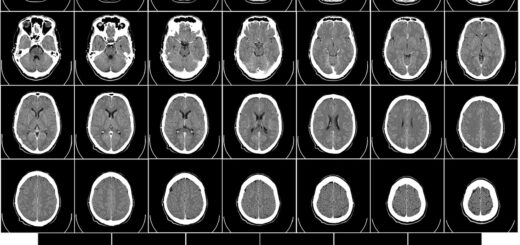

日誌 2019年9月12日 by 村上 徹 · Published 2019年9月12日 · Last modified 2025年11月22日 Week1 Day3 神経系、CT 全身にわたる系統から、神経系(脳は神経解剖学で)。 CTとDICOMビューア。今日インストールしよう! 小一時間以上掛かります。ファイル容量も1...